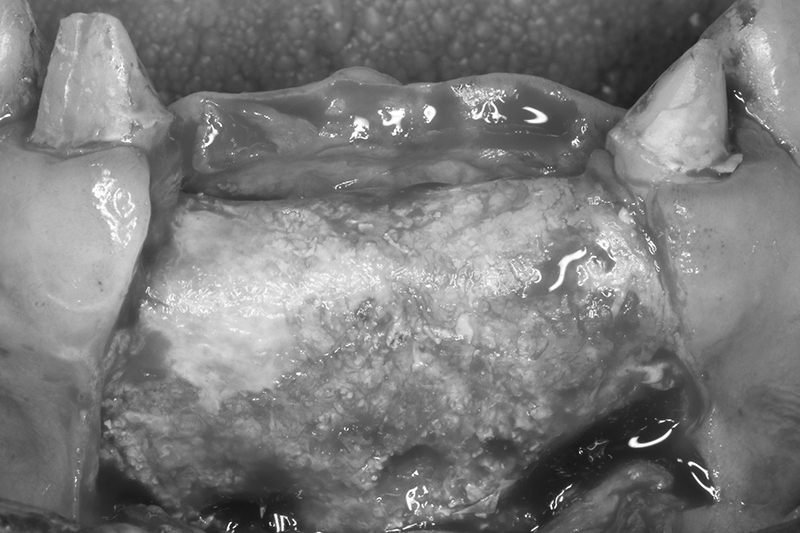

可見植體移除後骨缺損範圍大

取出的舊有one piece植體,舊式植體。